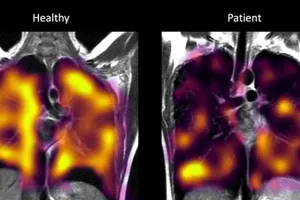

Anh có phát hiện quan trọng, mở ra hy vọng chấm dứt di chứng hậu COVID-19